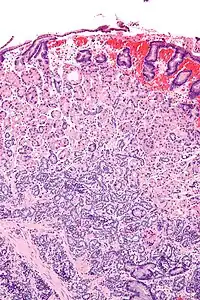

Micrograph of a neuroendocrine tumour of the stomach. H&E stain.